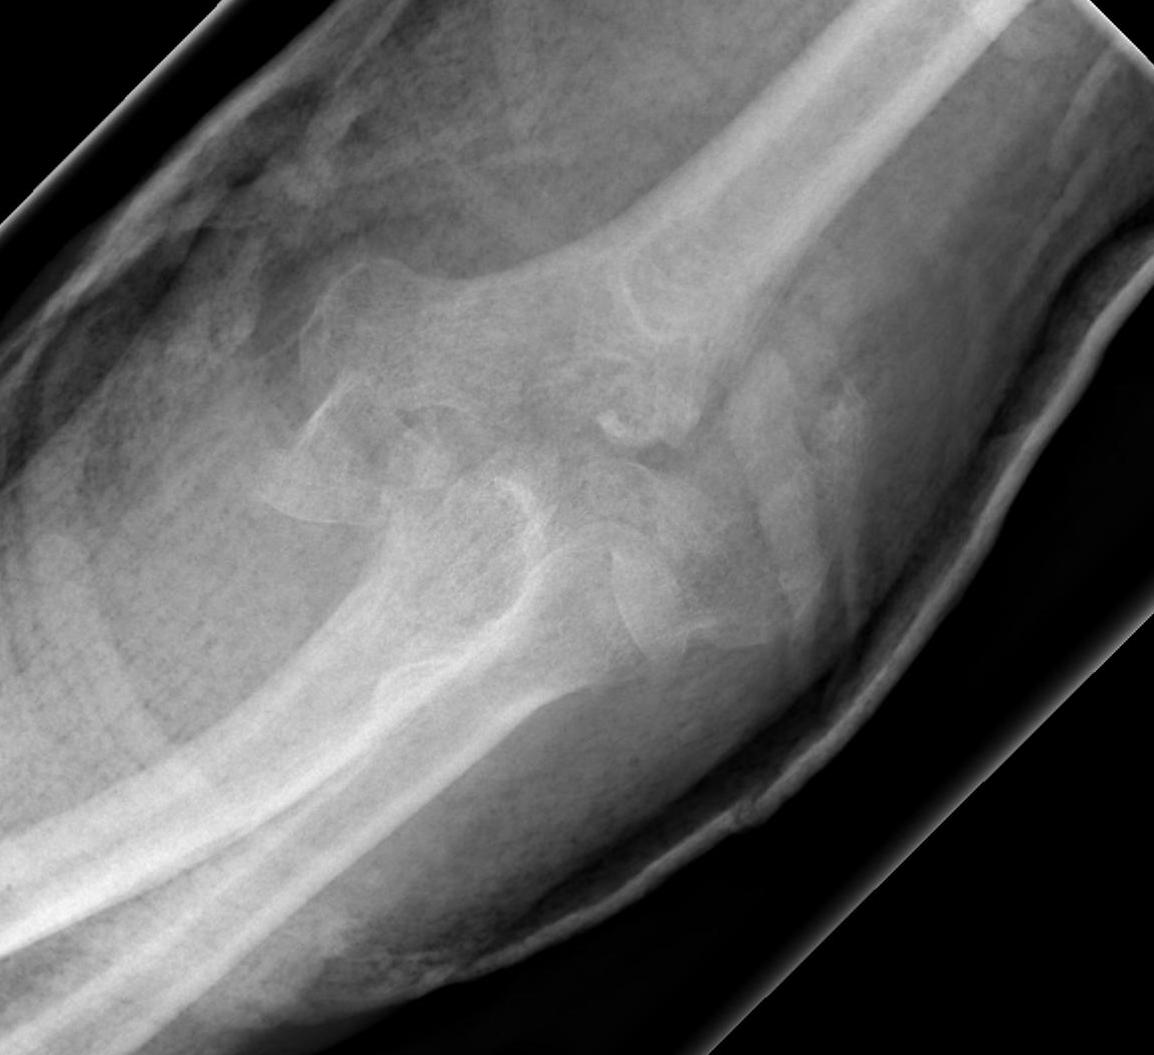

OTA / AO Classification

Type A: Extra-articular fracture

Type B: Partial articular fractures

Lateral condyle Medial condyle

Type C: Complete articular fractures

CT scan